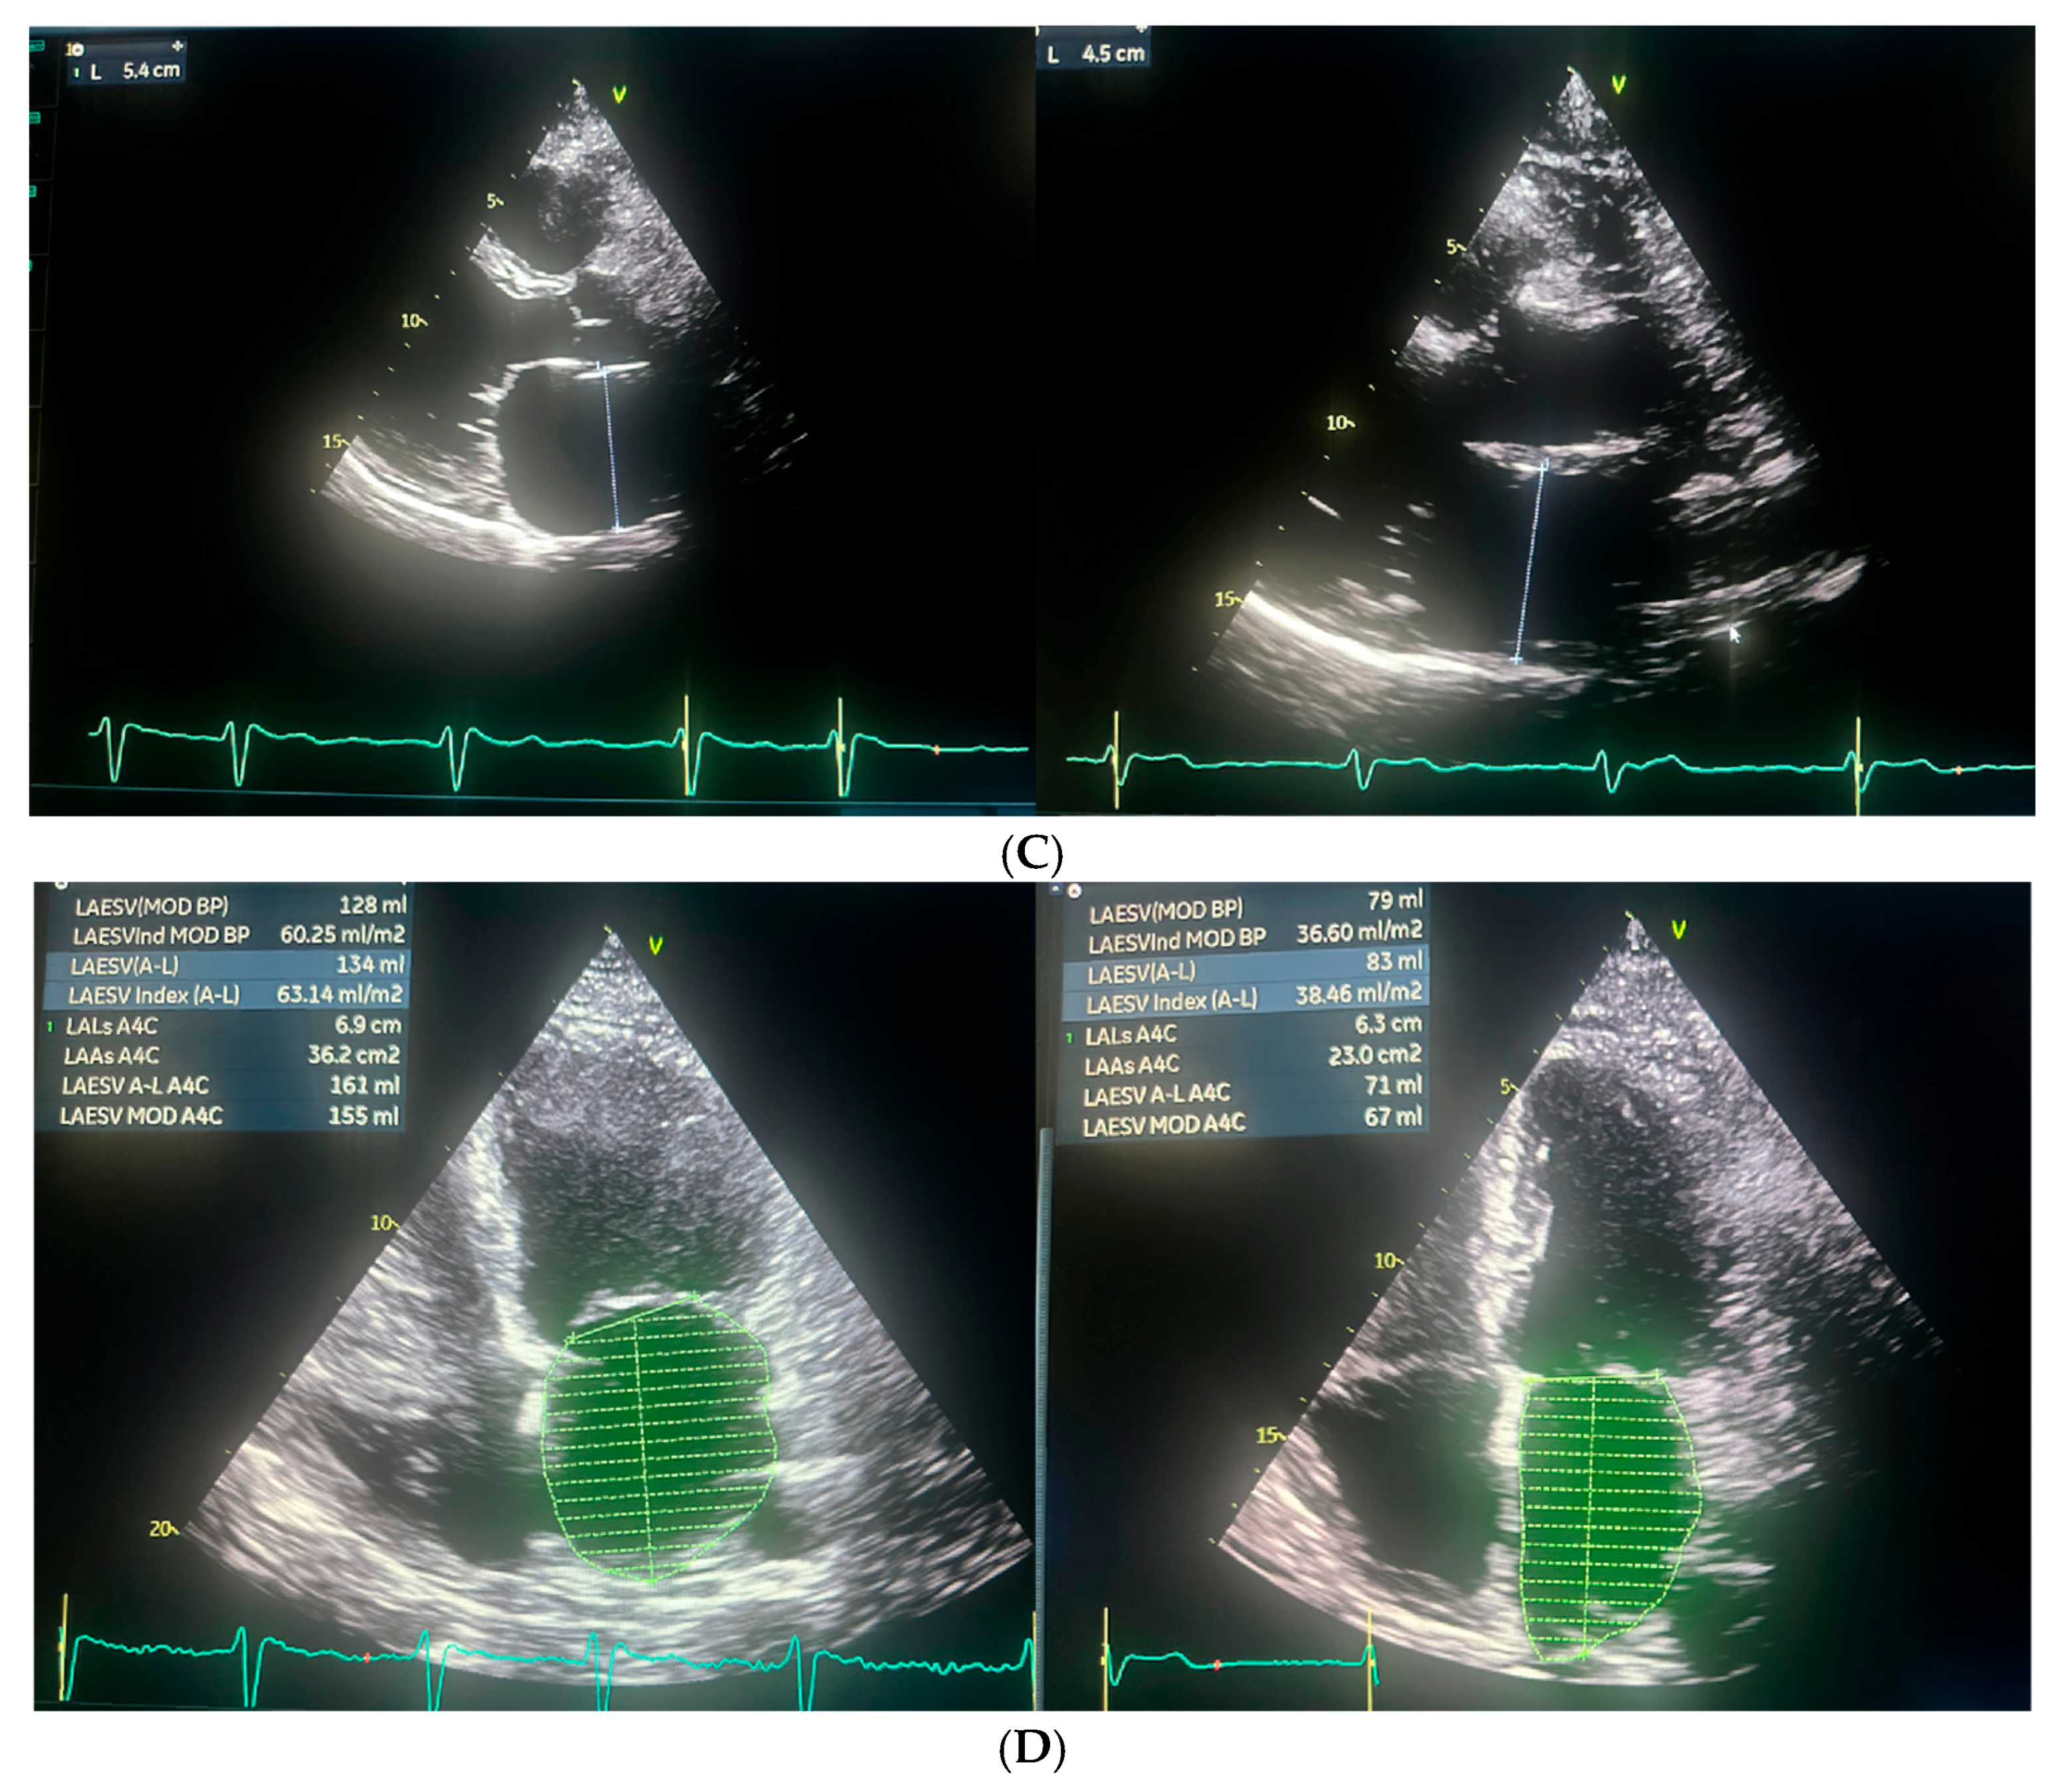

Repeated TTE demonstrated a slight improvement in left ventricular systolic function, with an LVEF of 25%. (Figure 3 and Figure 4).

Following the ablation procedure, chronic amiodarone therapy was discontinued. The patient was subsequently scheduled for follow-up visits approximately 2 months and 14 months after the intervention. Since the ablation, the patient remained in very good general condition, with no documented recurrences of arrhythmia, either symptomatically or on 24 h Holter ECG monitoring. There were no hospitalizations for arrhythmia-related events during this period. At the 14-month follow-up, TTE was performed and complete normalization of left ventricular systolic function was observed, with an LVEF of 55% (Figure 3 and Figure 4). Additionally, a reduction in the dimensions of both atria, the right and left ventricles, was noted. The previously elevated natriuretic peptide levels had also regressed significantly. Importantly, the patient’s functional status and quality of life improved markedly, as assessed by the ASTA questionnaire, with a score reduction from 24 points before the procedure to 0 points after ablation. General and echocardiographic parameters before and after ablation are presented in Table 2, Table 3 and Table 4 respectively.

Figure 3. The figure illustrates the changes in cardiac chamber dimensions as assessed by echocardiography, comparing measurements obtained before and after the ablation procedure. Echocardiographic parameters prior to ablation are displayed on the left, while post-ablation values are shown on the right. (A) Left Ventricle End Diastolic Volume (LVEDD) and myocardium; (B) Left Ventricle End Systolic Volume (LVESD); (C) Left atrium postero-lateral diameter; (D) Left atrium volume index (LAVI).